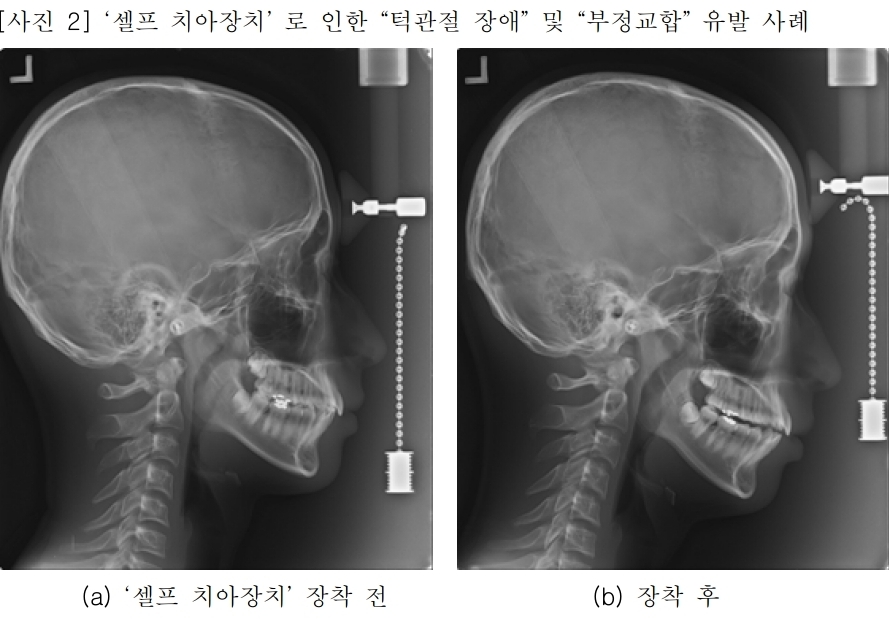

일부 온라인 쇼핑몰에서 치과의사의 진단 없이 이갈이, 코골이 방지 또는 치아교정 효과가 있는 것처럼 홍보하며 마우스피스를 판매하고 있다. 그러나 이러한 ‘셀프 치아장치’는 효과를 담보할 수 없을 뿐 아니라, 치아나 잇몸 손상, 부정교합, 턱관절 장애, 파손으로 인한 기도흡입 등 심각한 부작용을 유발하는 것으로 확인됐다.

실제로 건강한 생활을 위해 ‘셀프 치아장치’를 사용했다가 ▲치아 및 잇몸 손상 ▲부정교합 ▲턱관절 장애를 겪는 사례가 빈번하게 발생하고 있다. 한 소비자는 ‘셀프 이갈이 방지 장치’를 2주간 사용한 후 "양치와 음식 섭취가 고통스럽다"는 후기를 남겼으며, 구강 내 점막궤양이 유발된 것으로 보인다.